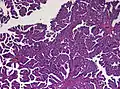

Histopathology

The tumor is neuroectodermal in origin and similar in structure to a normal choroid plexus. They may be created by epithelial cells of the choroid plexus. Papillary fronds lined by bland columnar epithelium are visible under the microscope. Normal absences include mitotic activity, nuclear pleomorphism, and necrosis.[10] Tumors have positive immunohistochemistry for cytokeratin, vimentin, podoplanin, and S-100.[11] Up to 20% of choroid plexus papilloma patients may test positive for glial fibrillary acidic protein (GFAP).[12] Studies have found that fourth ventricle cancers express more S100 than lateral ventricle tumors, and older patients (over 20 years) express more GFAP and transthyretin than younger patients.[13] Some individuals with choroid plexus papilloma have germline TP53 gene mutations, according to genetic analyses.[14] These cancers rarely exhibit nuclear p53 protein positivity. Aicardi syndrome, hypomelanosis of Ito, and 9p duplication are syndromic correlations of choroid plexus papilloma.

Micrograph of a choroid plexus papilloma. H&E stain.